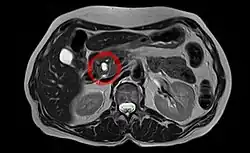

| Intraductal papillary mucinous neoplasm in magnetic resonance imaging. | |